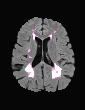

In recent years, data-driven machine learning (ML) methods have revolutionized the computer vision community by providing novel efficient solutions to many unsolved (medical) image analysis problems. However, due to the increasing privacy concerns and data fragmentation on many different sites, existing medical data are not fully utilized, thus limiting the potential of ML. Federated learning (FL) enables multiple parties to collaboratively train a ML model without exchanging local data. However, data heterogeneity (non-IID) among the distributed clients is yet a challenge. To this end, we propose a novel federated method, denoted Federated Disentanglement (FedDis), to disentangle the parameter space into shape and appearance, and only share the shape parameter with the clients. FedDis is based on the assumption that the anatomical structure in brain MRI images is similar across multiple institutions, and sharing the shape knowledge would be beneficial in anomaly detection. In this paper, we leverage healthy brain scans of 623 subjects from multiple sites with real data (OASIS, ADNI) in a privacy-preserving fashion to learn a model of normal anatomy, that allows to segment abnormal structures. We demonstrate a superior performance of FedDis on real pathological databases containing 109 subjects; two publicly available MS Lesions (MSLUB, MSISBI), and an in-house database with MS and Glioblastoma (MSI and GBI). FedDis achieved an average dice performance of 0.38, outperforming the state-of-the-art (SOTA) auto-encoder by 42% and the SOTA federated method by 11%. Further, we illustrate that FedDis learns a shape embedding that is orthogonal to the appearance and consistent under different intensity augmentations.